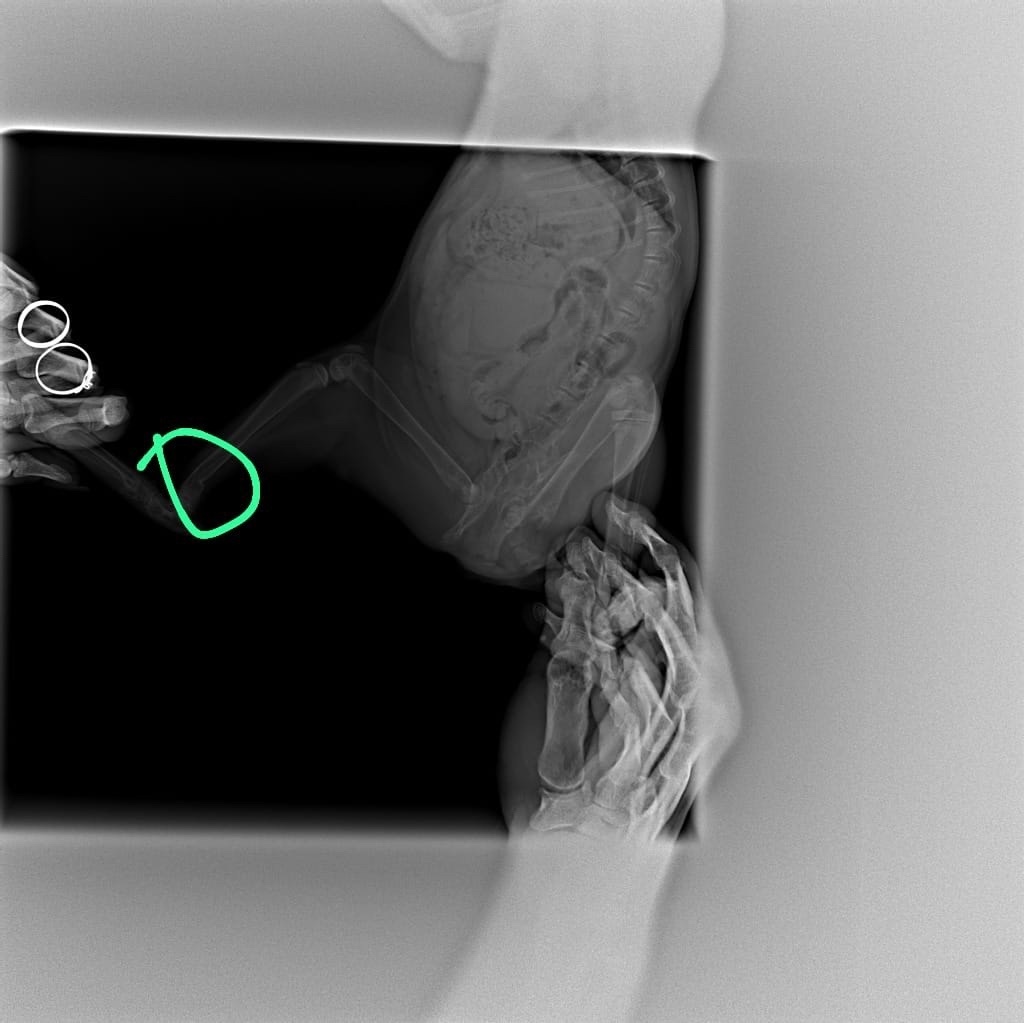

Однажды кто-то выбросил МЕСЯЧНОГО малыша на улицу… Котёнок был на столько мал, что не умел даже кушать самостоятельно. Но, на сей раз ему повезло, кроха был обнаружен семьей, которая и выкормила его. К сожалению, спасутся время, произошла tрагедия… Коненок залез в диван, им и был придавлен. Теперь малыш в приюте, так как лечить его денег у семьи НЕТ! У котёнка вторичный кормовой гиперпаратиреоз (рахит), в месячном возрасте отняли от матери и кормили молоком и мясом… Два переLома, оба по типу "зелёной ветки"...

Пeрелом шейки бедра левой тазовой конечности (подобный переLом был у нашего Снежка), второй переLом голени той же левой тазовой конечности! Все, что мы смогли, это сделать рентгены! Дальше НЕОБХОДИМ прием хирурга, лекарства, операция видимо, раз переLомы и спец корм. Так же АНАЛИЗЫ. Каждый день мы смотрим на этого малыша и понимаем, что время работает против нас! Ее глаза полны сtраха и ожидания, а мы бессильны помочь так, как он этого заслуживает. У ПРИЮТА НЕТ ДЕНЕГ, НЕТ ВРАЧЕЙ, НЕТ НЕОБХОДИМЫХ ЛЕКАРСТВ и опер стоит дорого! Мы ведь частный приют, где и так 500 животных…